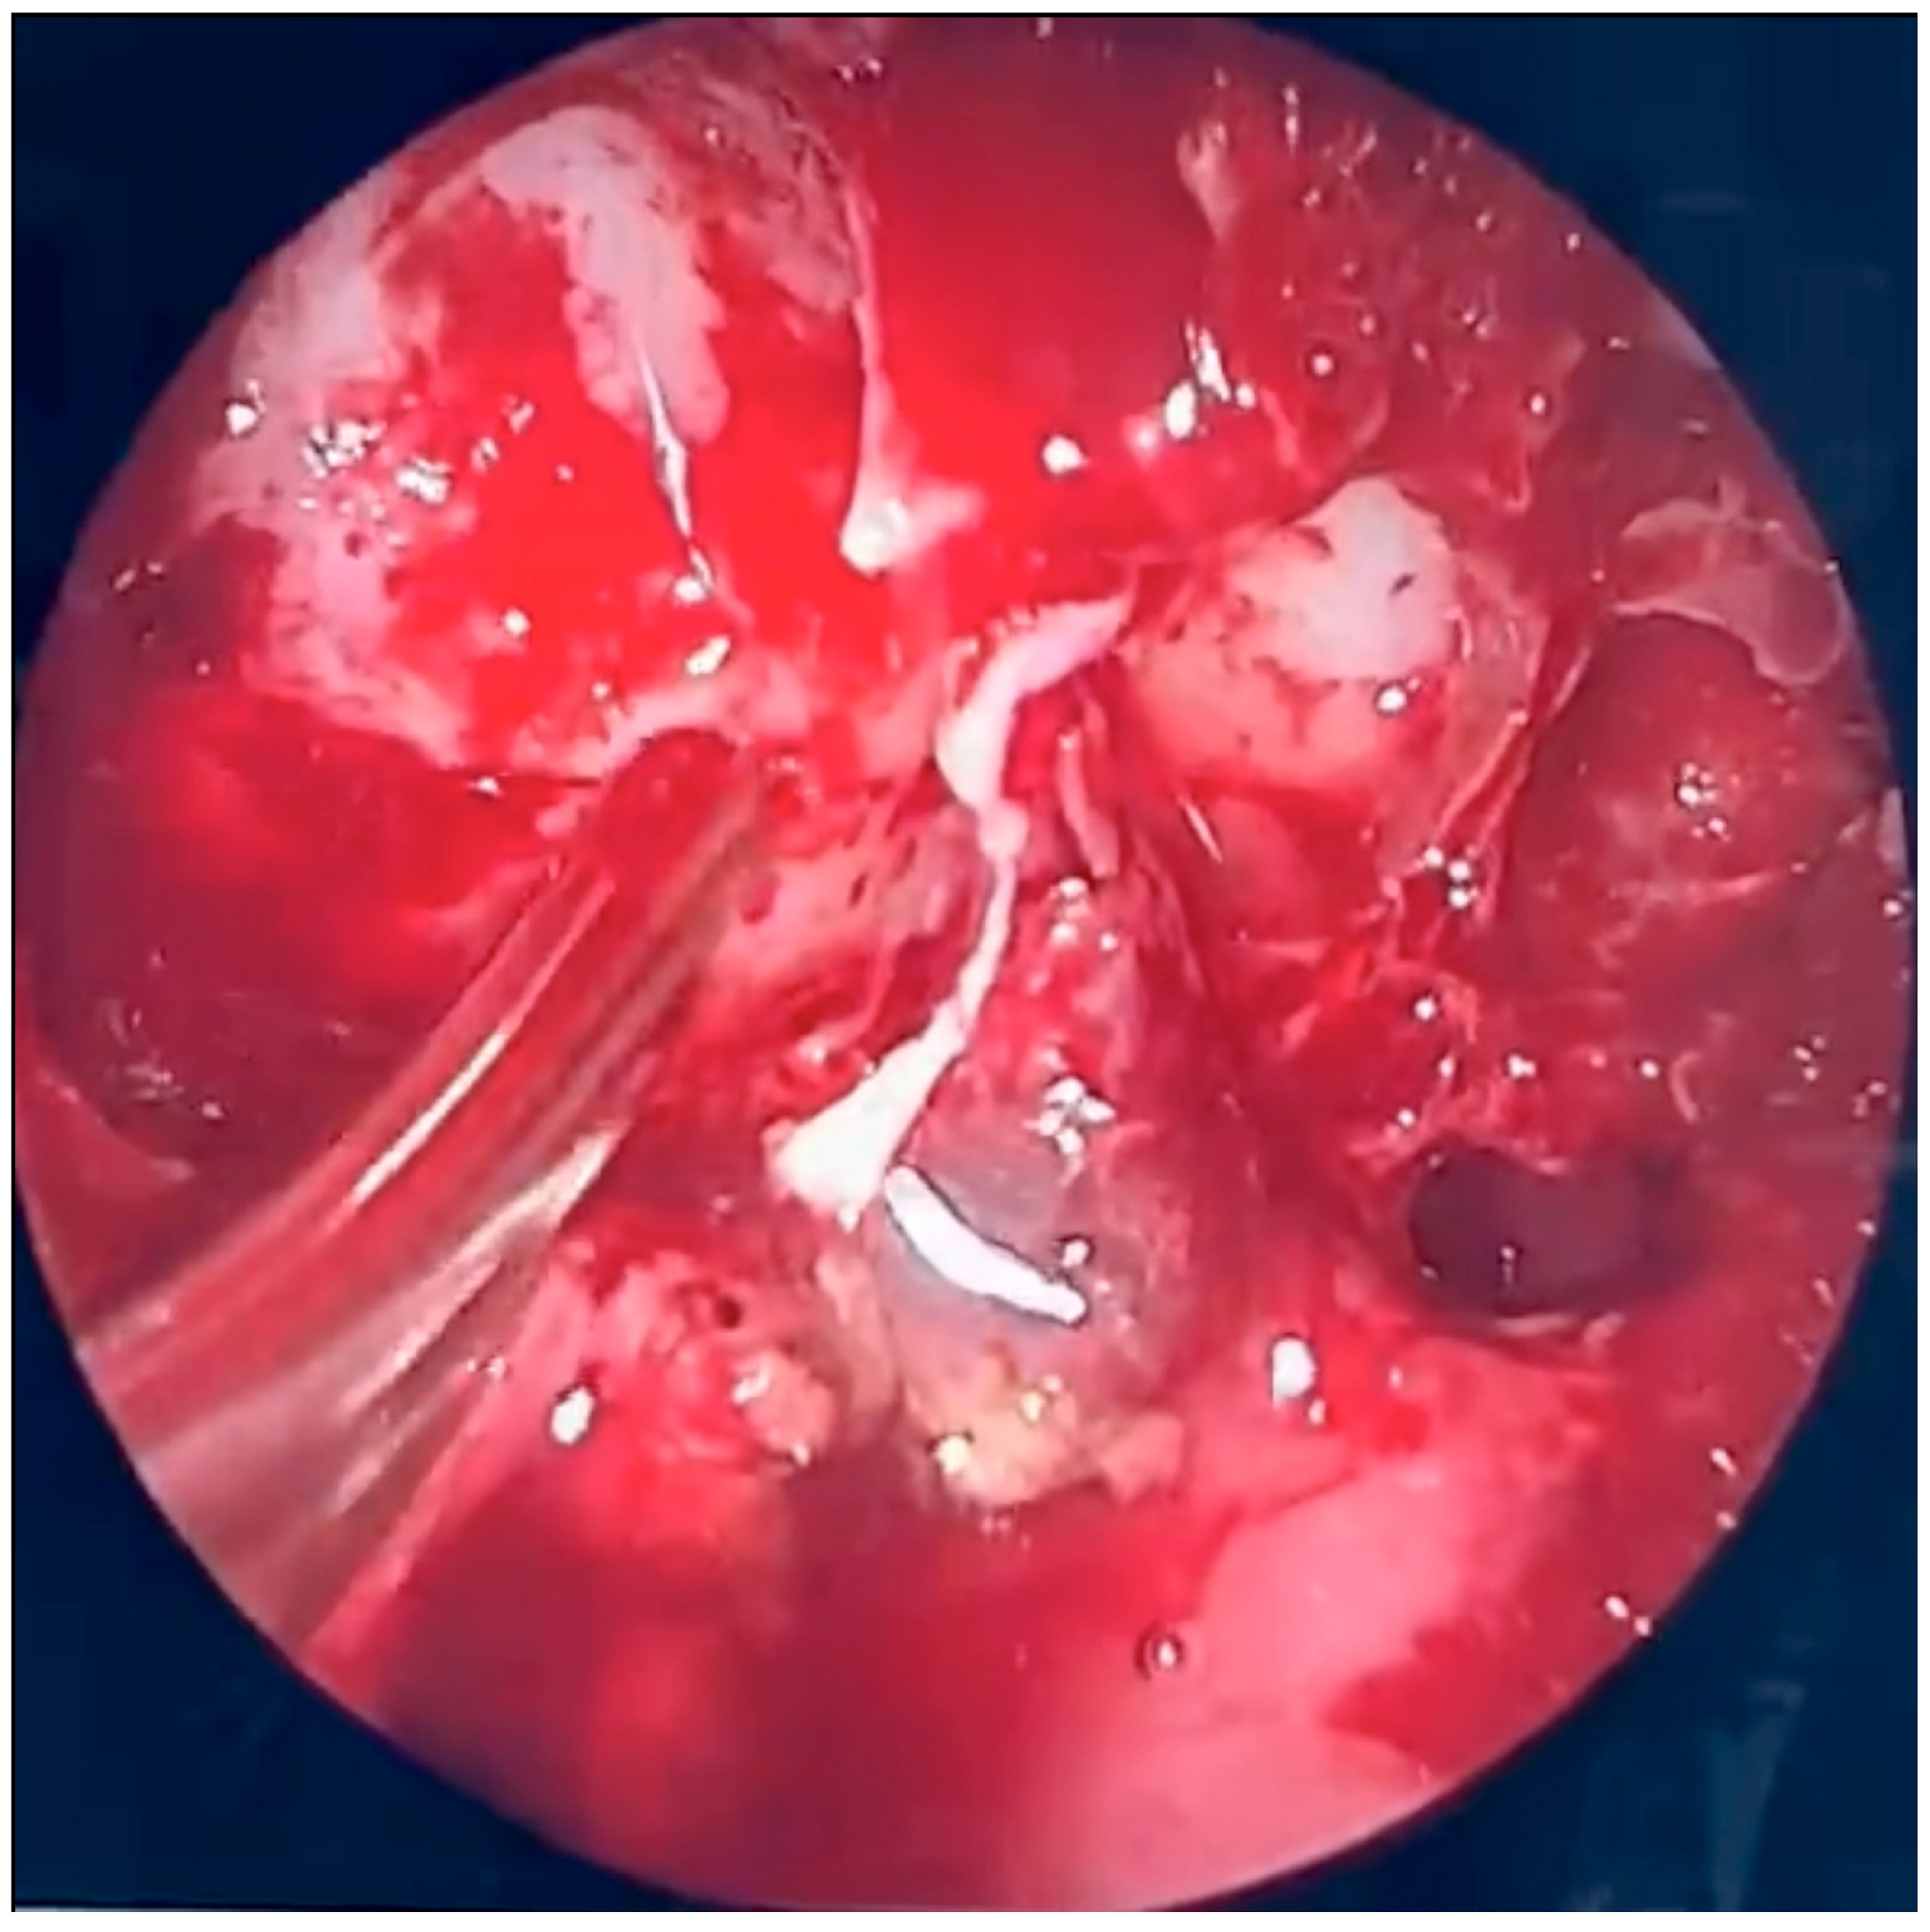

During further inspection, a bony defect of the lamina papyracea was identified in its anterior portion, measuring approximately 4 mm in diameter. The lamina papyracea was resected further, extending posteriorly to the level of the posterior ethmoid cells. A horizontal incision was then made in the orbital periosteum, which allowed for partial herniation of the orbital fat into the ethmoid cavity—facilitating access and drainage. Anterior nasal packing using Merocel was placed to support mucosal healing and maintain patency. Figure 3, Figure 4 and Figure 5 present the intraoperative view.

Figure 5. Endoscopic surgery: intraoperative view of the right maxillary sinus after removal of fungal masses. Opening of the sphenoidal sinus visible on the right (4 o’clock position).